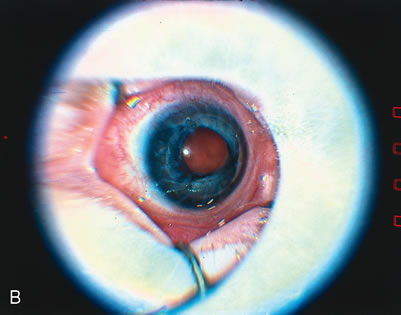

The indications for scleral buckling surgery are stage 4A with progression, stage 4B or open funnel stage 5 retinal detachment. Stage 4A retinal detachment (Fig. 7A) is subtotal, and spares the fovea. The CryoROP study demonstrated resolution in 46.1% of eyes with stage 4A retinal detachments at 4½ years. 61 Unfortunately, the study also showed a 17.9% risk of progression for stage 4A eyes to total retinal detachment. Stage 4B retinal detachment (Fig. 7B), which is due to progressive exudation or traction, involves detachment of the fovea. Stage 5 retinal detachment (Fig. 7C) is total; it may have an open or closed funnel configuration. When the detachment is funnel shaped, the funnel is divided into anterior and posterior parts, and may be open or closed in either location.

Fig. 7. A. Stage 4A ROP. Subtotal retinal detachment does not involve the fovea. B. Stage 4B ROP. Subtotal retinal detachment involves the fovea. C. Stage 5 ROP. Total retinal detachment. The detachment may be shallow, with an open funnel configuration, as in this example. Note the loss of the choroidal vascular pattern because of subretinal fluid.